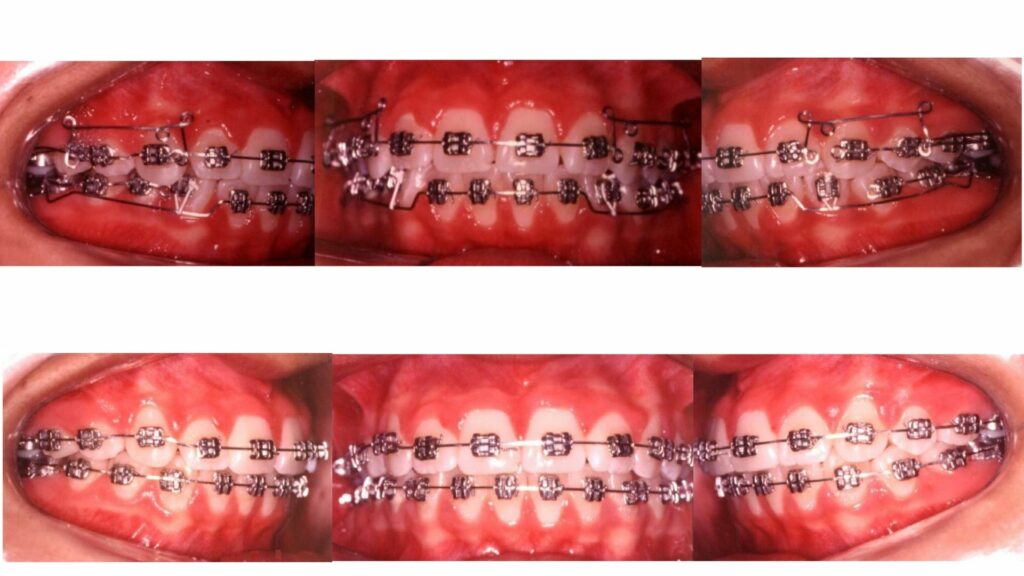

Os principais arcos usados na Ortodontia Bioprogressiva são feitos de um material especial chamado Elgiloy, que proporciona excelente ancoragem para o movimento dos dentes. Esse material permite que os dentes se movam sem sobrecarregá-los desnecessariamente, evitando efeitos indesejáveis.

O fio Elgiloy, com sua seção quadrada, facilita a movimentação dos dentes em diferentes tipos de ossos, tornando o tratamento mais eficiente e reduzindo o tempo necessário para alcançar os resultados. Ele também ajuda a corrigir as inclinações desfavoráveis dos dentes de forma mais rápida.